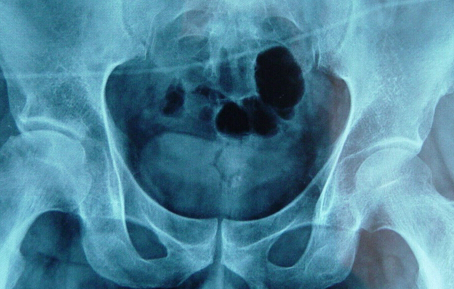

河南股骨头坏死专科医院介绍股骨头缺血坏死初期有什

河南股骨头坏死专科医院介绍股骨头缺血坏死是由于患者自身的病变破坏了股骨头的血液循环,…[详情]

河南治疗股骨头坏死医院:患上股骨头坏死的早期症状

河南治疗股骨头坏死医院介绍到股骨头坏死这种疾病在临床上是一种常见病,一种多发病,引起…[详情]